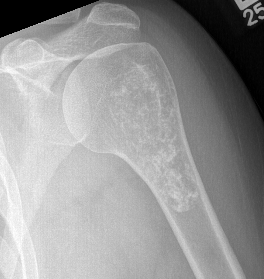

X-ray

Intralesional calcification - punctate, stippled calcification and broken rings

Differential diagnosis long bone with intralesional calcification

1. Enchondroma

2. Bone infarct

3. Chondrosarcoma